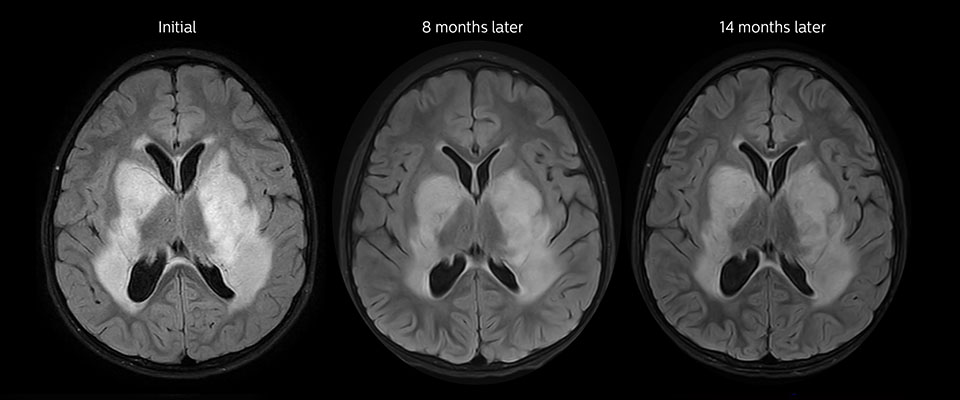

Low-grade glioma in a 5-year-old patient with neurofibromatosis 1. This low-grade lesion does not enhance on the post-contrast images, but does show an intermediate APT signal. The lesion stability over time confirms that it is a low-grade pathology.

Follow-up over time

MRI with APT post resection

Immediately post resection MRI was again performed. T2-weighted and postcontrast T1-weighted images are quite inconclusive for distinguishing residual tumor tissue from postoperative tissue changes. On the APT image some high signal is still seen, which would suggest residual tumor tissue.

Follow-up over time

In later follow-up scans the post-contrast T1-weighted images suggest recurrent tumor growth. So, it would be interesting to study the predictive value of APT in a large patient group.